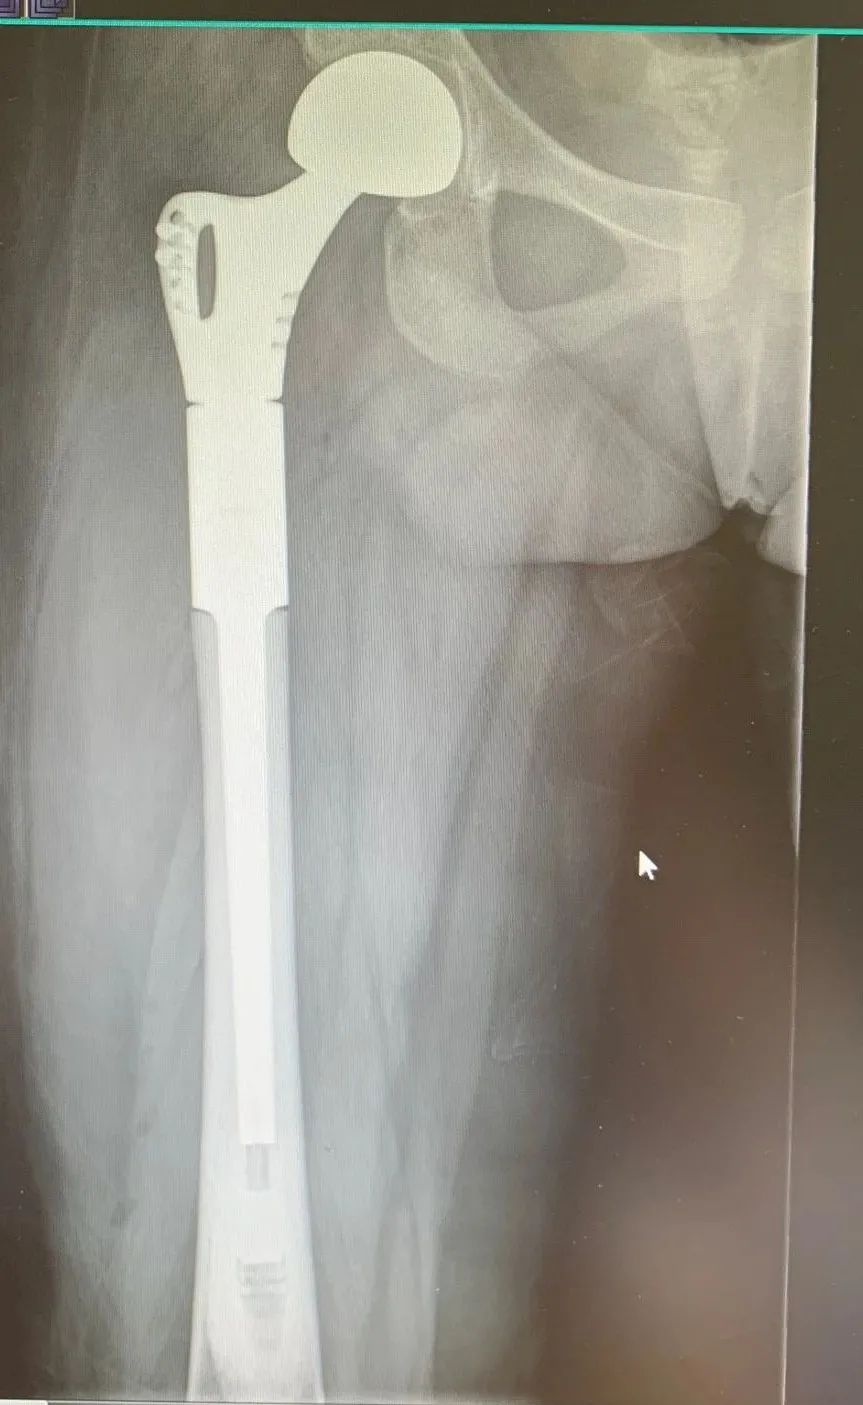

骨肿瘤康复治疗组早期介入股骨大段髋置换、膝关节肿瘤假体置换、半骨盆置换、全椎体置换等复杂骨肿瘤术后,在缓解症状同时改善患者的各项功能,维护患者的生命尊严。

股骨大段髋置换术后第5天坐起及行走训练